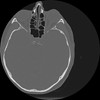

7 HUESO,,Vol,0.5,HUESO,,